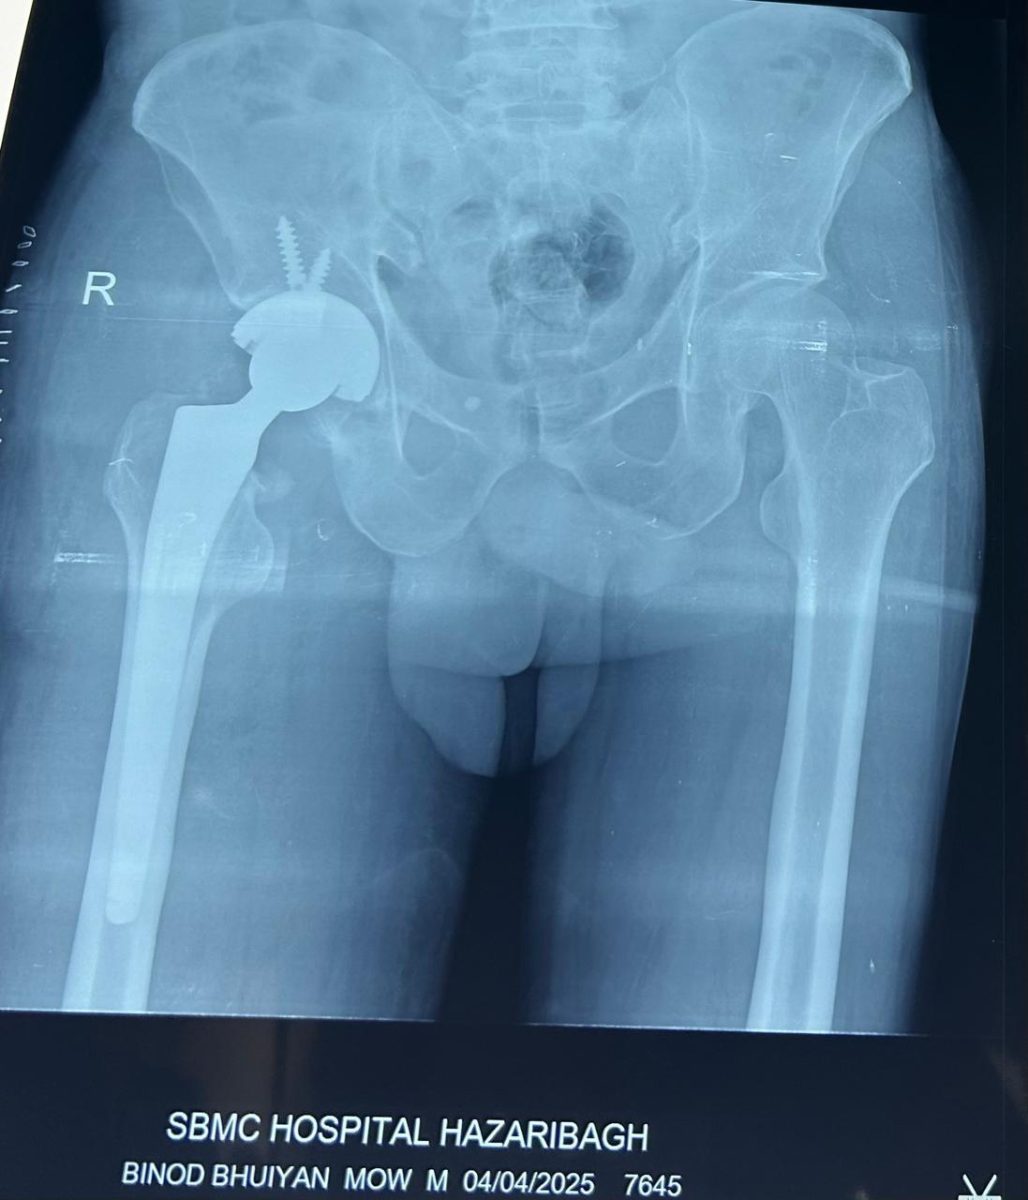

The patient underwent uncemented total hip replacement via a Direct Lateral ( Hardinge) approach. Intraoperative findings included a resorbed femoral neck and compromised head vascularity, confirming the decision for arthroplasty. An uncemented acetabular cup and femoral stem were implanted, with ceramic-on-polyethylene articulation. The procedure lasted approximately 90 minutes and was completed without any complications.

Patient was discharged on the 6th postoperative day with a home-based physiotherapy program. He was advised on hip precautions, strengthening exercises, and gradual progression to independent walking. At 6-week follow-up, he was ambulating confidently with a walking stick, pain-free, and had resumed many of his daily activities. Radiographs showed a well-positioned, stable prosthesis with no signs of loosening.